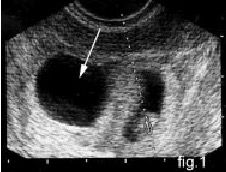

Q.12. What's the finding on USG?

Correct Answer : D

Q.13. What's the finding on USG?

Correct Answer : C

Q.14. What do you see?